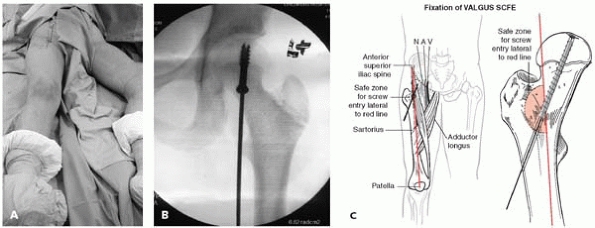

▪ FIGURE 22-16

The “valgus SCFE” can be trouble. Achieving fixation with proper screw orientation may put the neurovascular bundle at risk. This photo (A) shows positioning of the guidewire in the anterior thigh. The fluoroscopic image (B) shows the screw oriented perpendicular to the physis. (C) The relationship between the guidewire trajectory and the neurovascular bundle. (Case and pinning concepts courtesy of R. Davidson, MD.) (C) Staying out of trouble pinning a valgus SCFE. The safe zone for the screw is just lateral to the red line drawn here between the anterior-superior iliac spine and the center of the patella. The femoral head sits very superiorly and almost laterally on the neck of the femur. A very vertical track should be taken from distal to proximal in order to get a screw across the physis.  |

epiphysis presents certain challenges. The perfect trajectory for a pin

may put the neurovascular bundle at risk27 (Fig. 22-16).